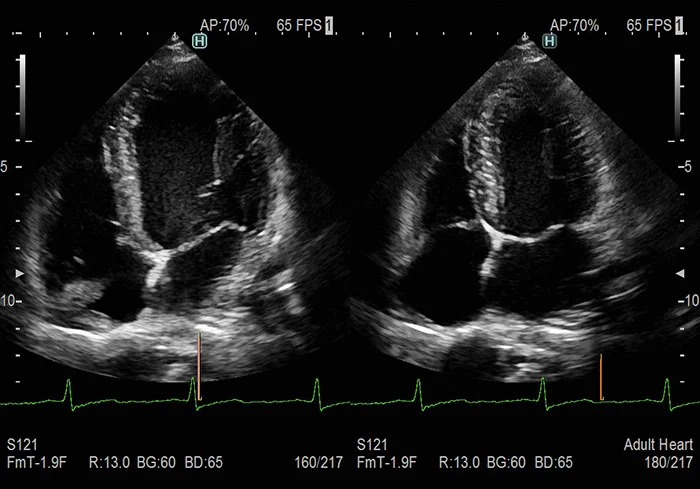

Виртуальное контрастирование левого желудочка сердца

Исследование сердца технически сложных пациентов может вызвать трудности в любом кабинете эхокардиографии. Обычно, в таких случаях для визуализации границ эндокарда используются контрастные препараты. К сожалению, применение контрастного вещества увеличивает длительность и стоимость процедуры, а – самое важное – процедура становится инвазивной.

Один из инструментов набора HDAnalytics под названием LV eFlow был специально разработан для улучшения дифференциации сигналов от кровотока и сигналов от тканей сердца. В ряде случаев эта технология может стать альтернативой применению контрастных веществ.

LV eFlow – это высококачественный режим отображения кровотока в левом желудочке с увеличенным пространственным и временным разрешением. Режим обеспечивает улучшенную визуализацию границ эндокарда. По сравнению с привычными методами, этот режим позволяет достичь визуализации потоков с повышенной чувствительностью и чёткостью.

Таким образом, применение LV eFlow может значительно облегчить технически сложное исследование и позволяет получить результат без использования контрастных веществ.